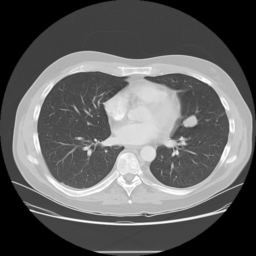

![]() |

| (a) | (b) | (c) | (d) |

Unsupervised Categorization: Our category discovery clusters are generally visually coherent within the cluster and size-balanced across clusters. However, image clusters formed only based on text information (of radiology reports) are highly unbalanced [49], with three clusters inhabiting the majority of images. Note that our method imposes no explicit constraint on the number of instances per cluster. Fig. 6 shows sample images and their top-10 associated key words from two randomly selected clusters (more results are provided in the supplementary material). The LDPO clusters are found to be clinically or semantically related to the corresponding key words, which describe presented anatomies, pathologies (e.g., adenopathy, mass), their associated attributes (e.g., bulky, frontal) and imaging protocols or properties.

The category discovery clusters employing our LDPO method are found to be more visually coherent and cluster-wise balanced in comparison to the results in [49] where clusters are formed only from text information ( radiology reports). Fig. 7 Left shows the image numbers for each cluster from the AlexNet-FC7-Topic setting. The numbers are uniformly distributed with a mean of 778 and standard deviation of 52. Fig. 7 Right illustrates the relation of clustering results derived from image cues or text reports [49]. Note that there is no instance-balance-per-cluster constraints in the LDPO clustering. The clusters in [49] are highly uneven: 3 clusters inhabit the majority of images. Fig. 6 shows sample images and top-10 associated key words from 5 randomly selected clusters (more results in the supplementary material). The LDPO clusters are found to be semantically or clinically related to the corresponding key words, containing the information of (likely appeared) anatomies, pathologies (e.g., adenopathy, mass), their attributes (e.g., bulky, frontal) and imaging protocols or properties.